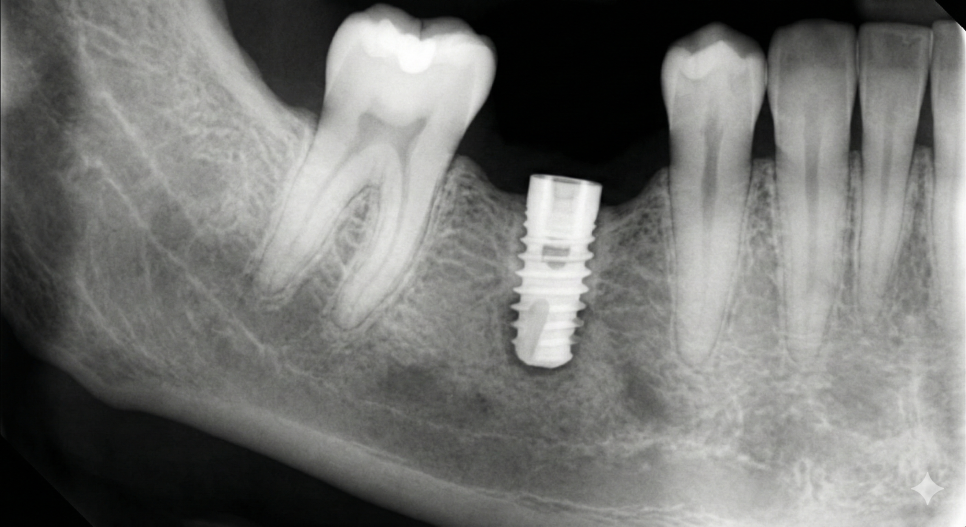

임플란트 식립과 골유착의 과정

기반이 준비되었다면

이제 본격적으로 임플란트를 식립하게 됩니다.

단순히 심는 것으로 끝나는 것이 아니라,

식립된 임플란트와 환자 본인의 뼈가

단단하게 붙는 '골유착' 기간이 필요하죠.

이 기간은 환자분의

골질이나 건강 상태에 따라

수개월 정도 소요될 수 있으며,

이 시기를 얼마나 안정적으로 보내느냐가

전체 치료의 성패를 좌우하기도 합니다.

이 과정에서 발생할 수 있는 불편을 줄이고

성공률을 높이기 위해 디지털 장비를 활용해

식립 위치를 결정합니다.